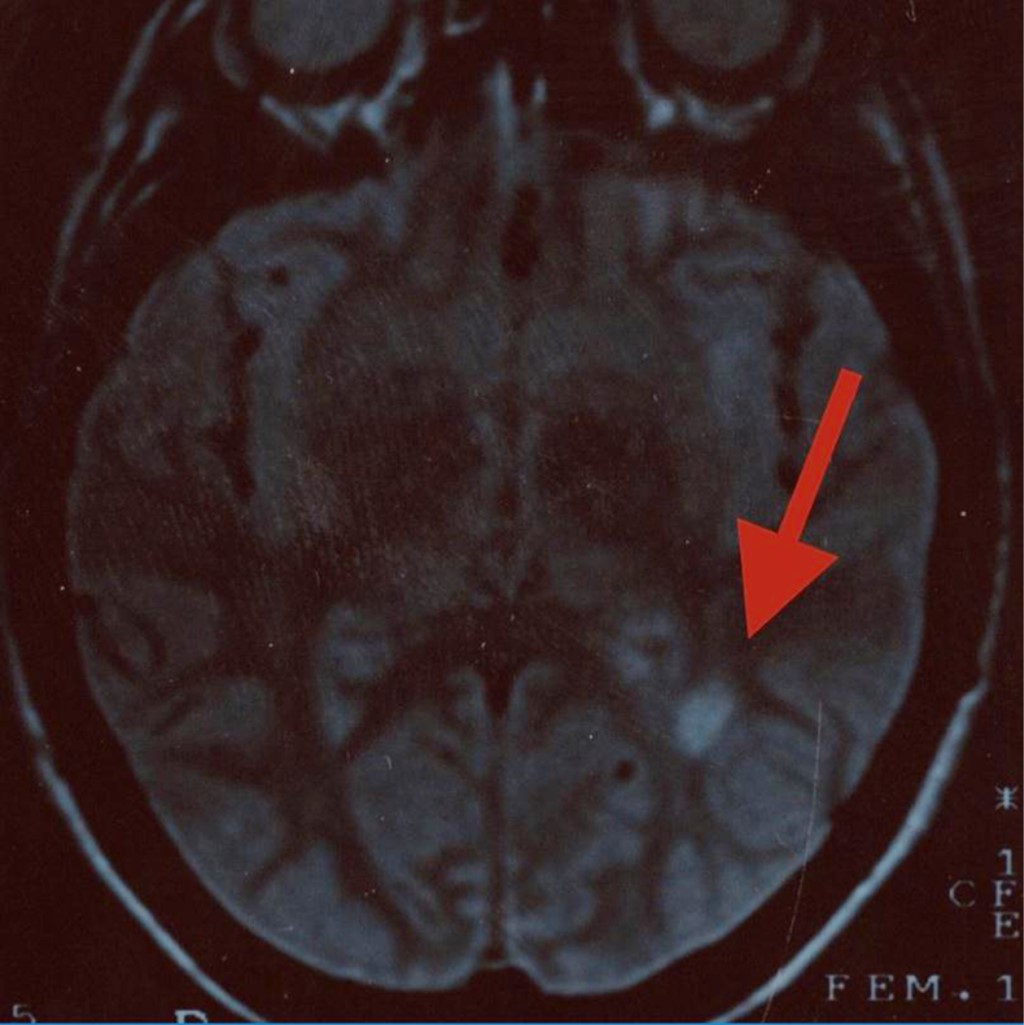

Objective: We describe two adolescent patients with multiple sclerosis, which is a demyelinating disease of the central nervous system. Presentation of the cases: The first case was a 14-year-old female patient with overweight; her condition was characterized by dizziness, headache, paresthesia in the lower limbs, diplopia and bradylalia. On physical examination, compatible data of cerebellar involvement were identified. A magnetic resonance imaging (MRI) of the skull showed areas of demyelination in the posterior fossa. Multiple sclerosis, the relapsing-remitting variety, is diagnosed. After the administration of steroids and beta interferon, there was improvement in symptoms. Second case: 13-year-old female, who presented fall from her own height, bladder incontinence, loss of strength in the left arm and leg. On physical examination, left hemiparesis was detected. MRI: demyelination data in lateral ventricle, cerebellum and spinal cord. The patient improved after starting steroids and interferon. Conclusions: The clinical presentation of multiple sclerosis in pediatric patients is a challenge, since it is a condition with unspecific manifestations. Establishing the diagnosis requires multiple studies. The earlier treatment is started, the more favorable the prognosis.

Figure 1